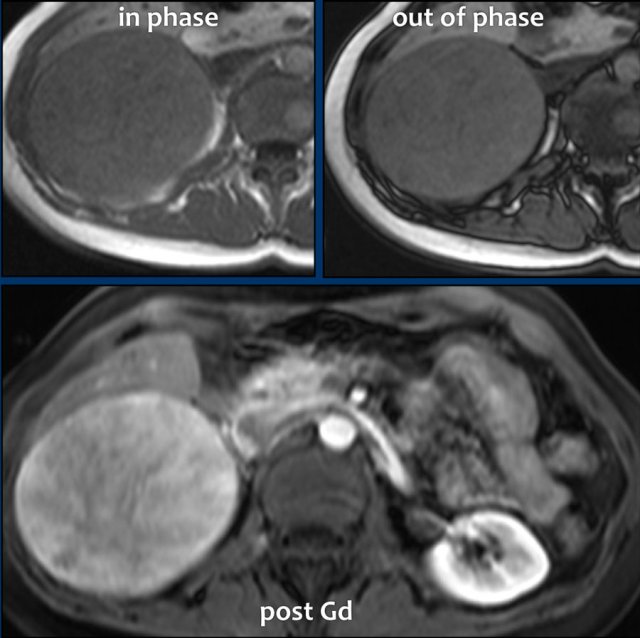

Atypical adenoma with no signal drop and heterogeneous enhancement. Atypical adenoma with no signal drop and heterogeneous enhancement.

These images are of a very atypical large adenoma.

There is no signal drop on the opposed phase image.

The post contrast image shows heterogeneous enhancement.

On resection this proved to be an adenoma, however.